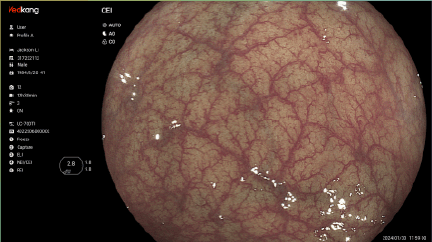

The Vedview U7 integrates cutting-edge innovations into a unified endoscopic platform, transforming future-oriented clinical visions into tangible reality today. Its premium capabilities - once beyond reach - are now readily accessible, empowering you to surpass conventional limits and achieve exceptional performance in endoscopic practice.

Dual Light Display Educational tool to shorten learning curve on optical chromoendoscopy image, by si- multaneously comparing white light image and chromoendoscopy image in real time